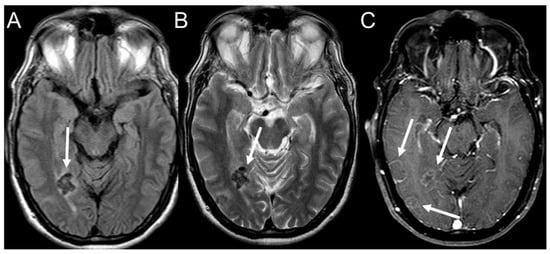

- Rosa Junior, M.; Baldon, I.V.; Amorim, A.F.C.; Fonseca, A.P.A.; Volpato, R.; Lourenco, R.B.; Baptista, R.M.; de Mello, R.A.F.; Pecanha, P.; Falqueto, A. Imaging paracoccidioidomycosis: A pictorial review from head to toe. Eur. J. Radiol. 2018, 103, 147–162. [Google Scholar] [CrossRef]

- Rosa Junior, M.; Amorim, A.C.; Baldon, I.V.; Martins, L.A.; Pereira, R.M.; Campos, R.P.; Goncalves, S.S.; Velloso, T.R.G.; Pecanha, P.; Falqueto, A. Paracoccidioidomycosis of the Central Nervous System: CT and MR Imaging Findings. AJNR Am. J. Neuroradiol. 2019, 40, 1681–1688. [Google Scholar] [CrossRef]

- Rosa, J.M.; Grenfell, M.L.R.; PeCanha, P.M. Hippocampal sclerosis in paracoccidioidomycosis. Arq. Neuropsiquiatr. 2020, 78, 384. [Google Scholar] [CrossRef]